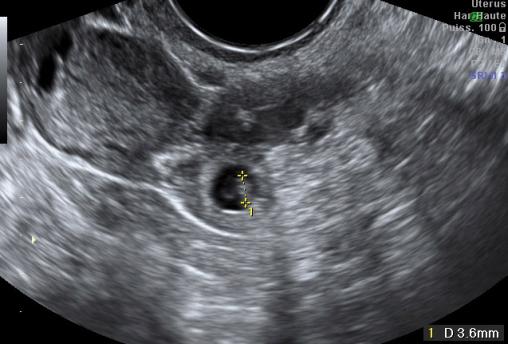

Sac gestationnel extra-utérin

Sac gestationnel extra-utérin avec vésicule ombilical et embryon mesurant 3,6 mm.